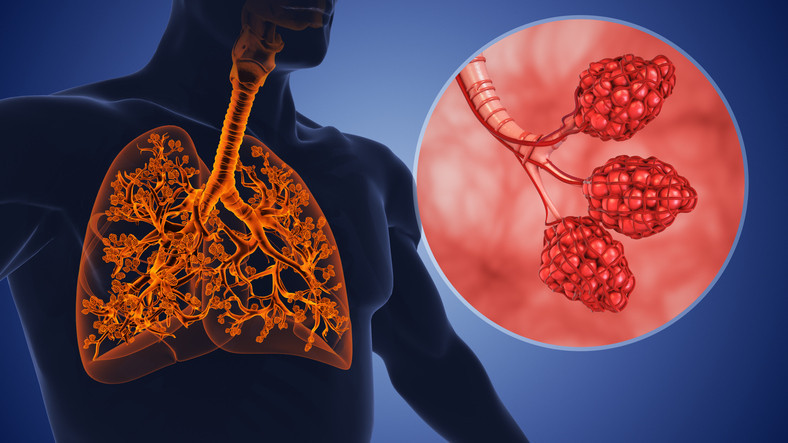

KOAH, hava kesecikleri olan bronşların daralması sonucu akciğerde elastikiyet kaybı, nefes darlığı, öksürük ve hava akımının kısıtlanması ile ortaya çıkan kronik inflamatuar bir akciğer hastalığıdır. KOAH, amfizem ve kronik obstrüktif bronşiti de içerir.

Kronik bronşit, en az iki yıl üst üste görülen ve bu iki yılın en az üç ayında semptomları ilerleyici bir rahatsızlık olarak bilinir. Amfizem ise, kana oksijen taşınmasını sağlayan hava keseciklerinin esnekliğini kaybetmesine neden olan bir hastalıktır.